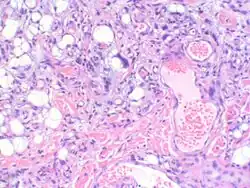

Myxofibrosarcoma-pathology -

Myxofibrosarcoma-pathology